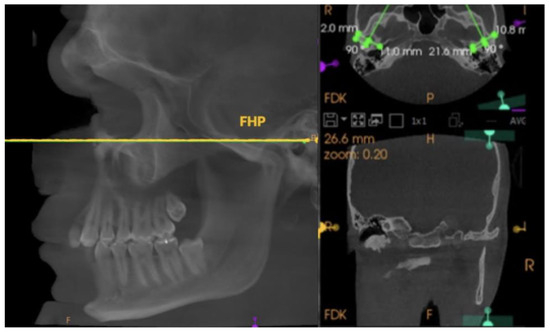

2. Materials and Methods